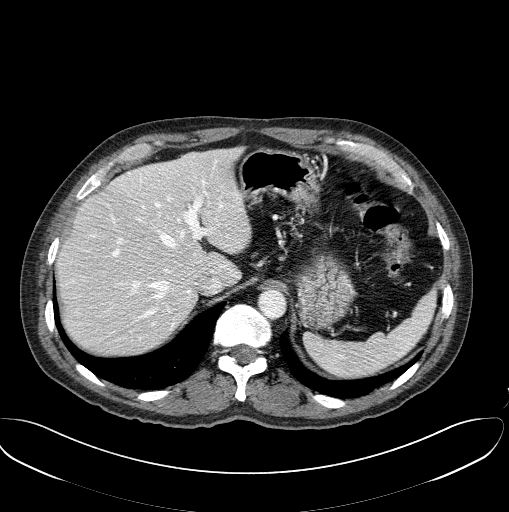

In March 2019 we started a collaboration with Mr Ali Emre Kavur (), a PhD student from Dokuz Eylul University in Izmir, Turkey, and his group. The purpose is to improve on the state-of-the-art in segmenting abdominal organs from CT and MRI images. Our hypothesis is that ensemble methods (combination of segmenters) will lead us to this improvement.

We discovered that an ensemble of "vanilla-style" deep learning segmentors offers an excellent solution to the problem if liver segmentation from 3D CT images.

Kavur, A. E., L. I. Kuncheva and M. A. Selver, Basic ensembles of vanilla-style deep learning models improve liver segmentation from CT images, arXiv:2001.09647 [eess.IV], 2020.